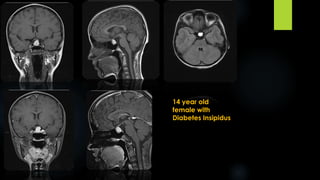

14 year old

female with

Diabetes Insipidus

14 year old femalewith Diabetes Insipidus